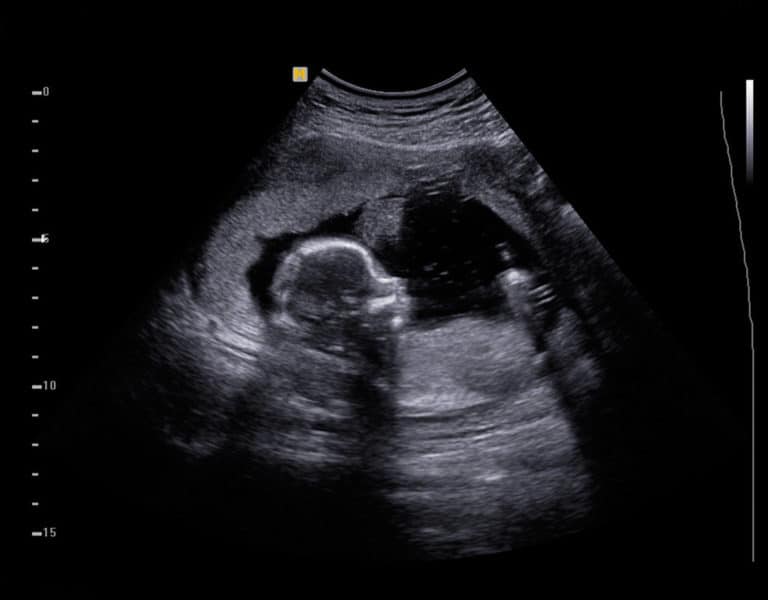

À quel âge un bébé se du ventre au dos ? Sang D'encre. Comprenez les étapes du développement et les signes à surveiller pour assurer le bien-être de votre enfant Quand bébé doit-il se retourner dans le ventre ? Les mouvements fœtaux sont une partie passionnante de la grossesse, et l'un des jalons les plus attendus est lorsque le bébé se retourne dans le ventre